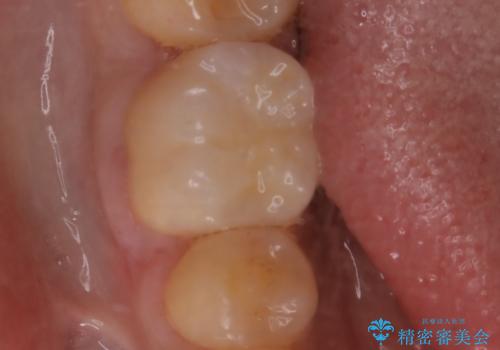

- セラミックへのやり替えを希望された患者様です。

日常的に食いしばる癖があり、歯の表面にはエナメルクラック(歯の表面にできる細かい破折線)も複数認められたため、セラミッククラウンによる治療をご提案しました。

歯ぎしりや食いしばりの癖がある方にはナイトガードの使用も併せてお勧めしています。

就寝時の歯ぎしり食いしばりのコントロールにはボツリヌストキシン注射も有効です。